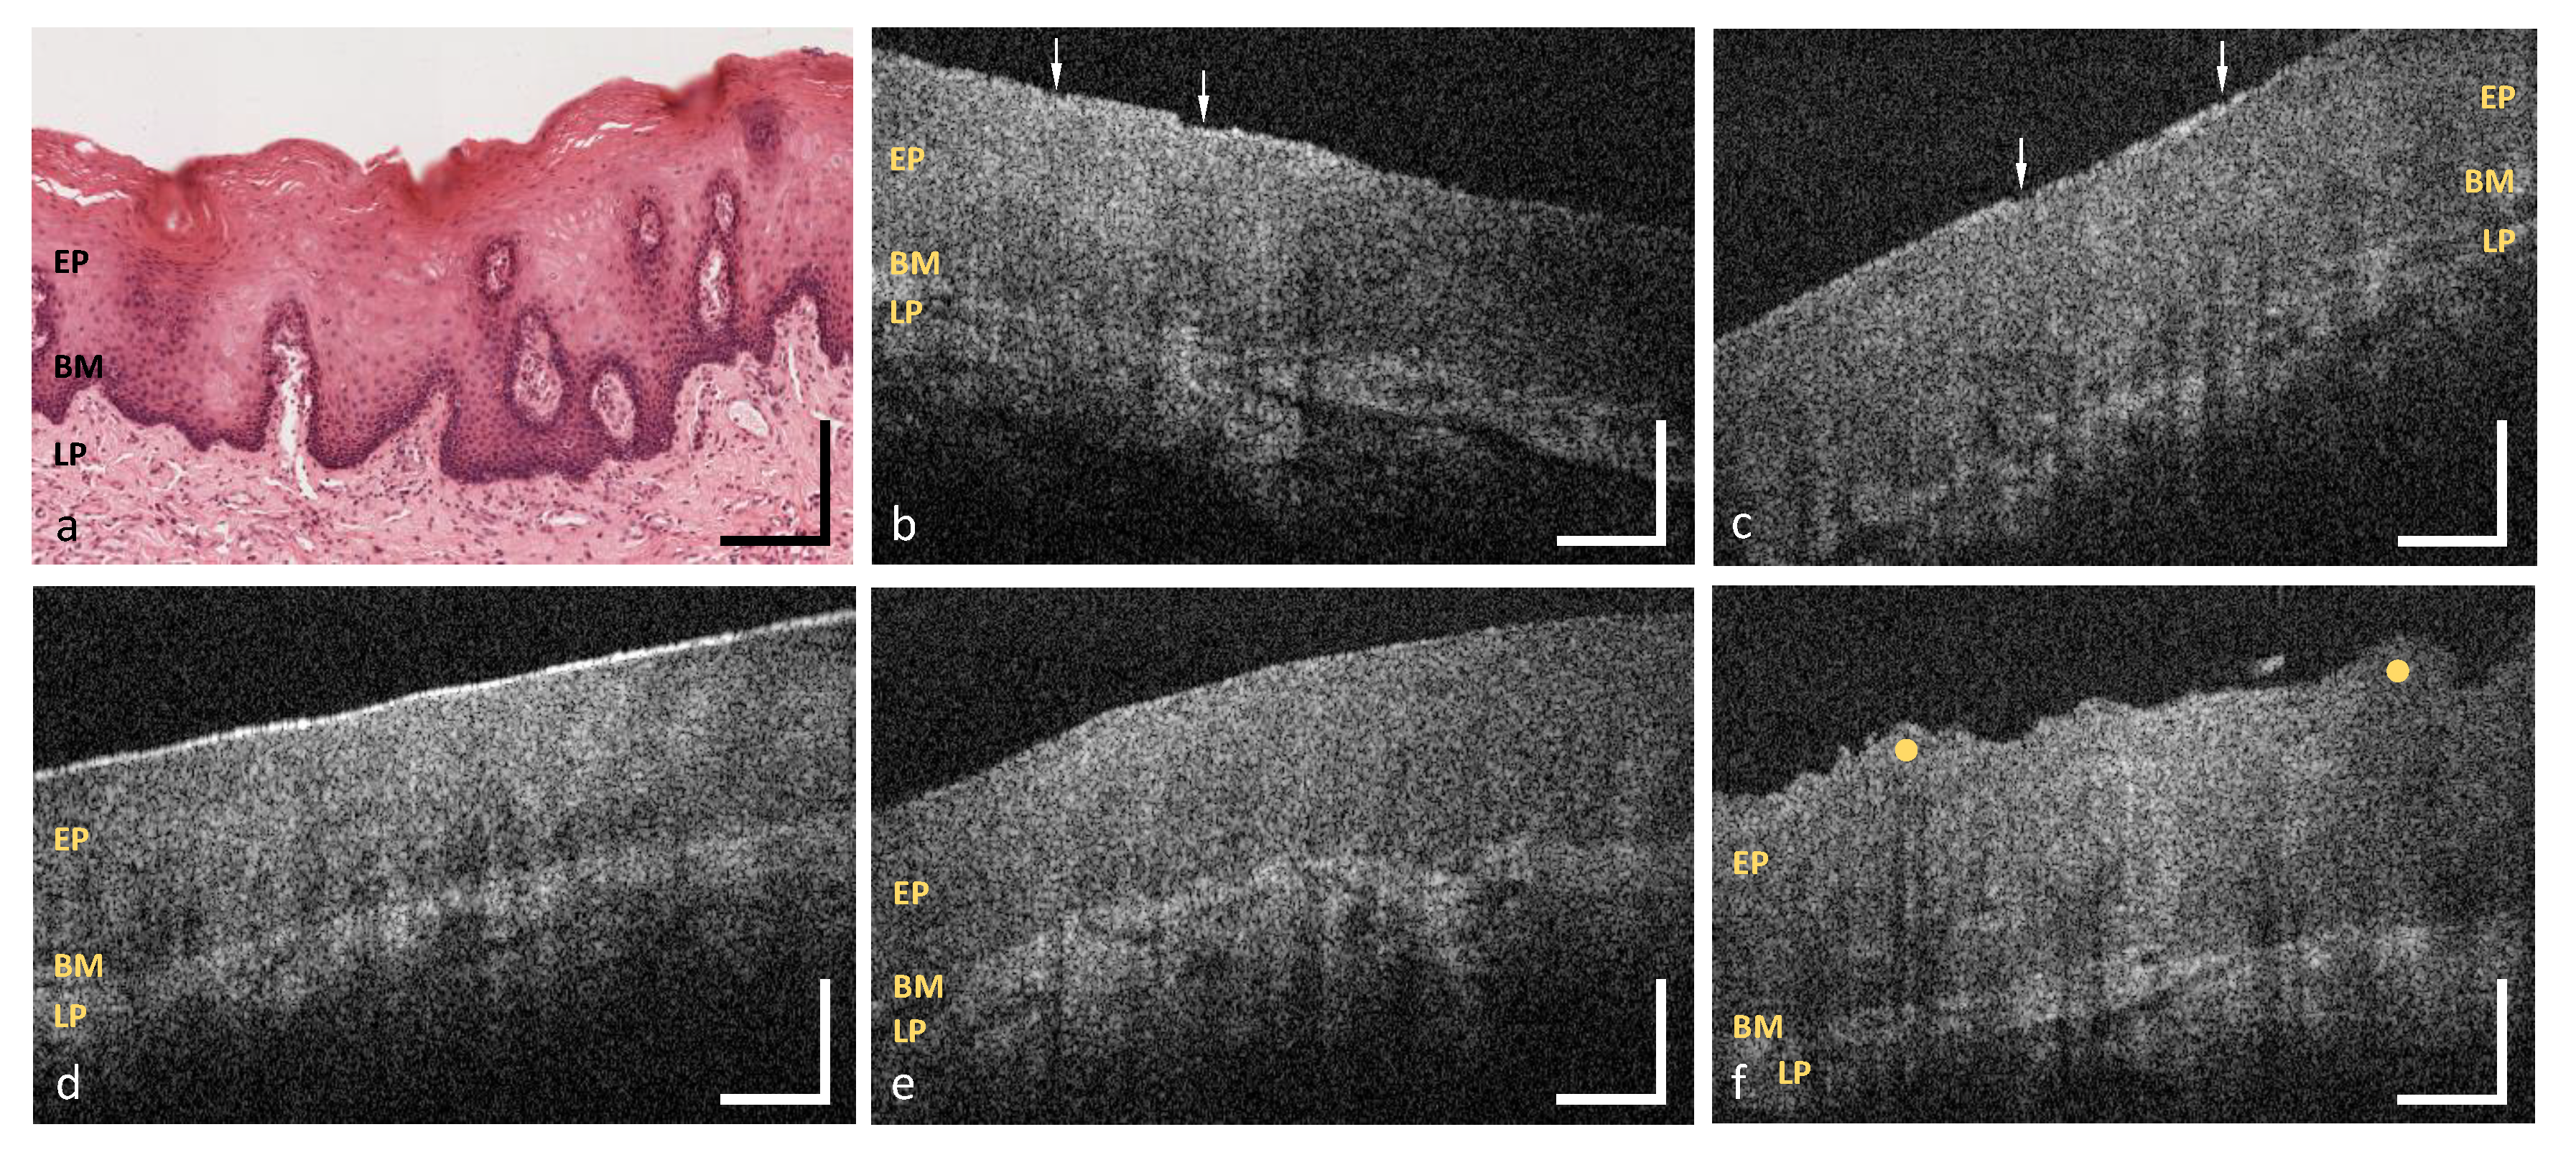

3.1. Labial and Alveolar Mucosa

3.2. Buccal Mucosa

3.3. Sublingual Mucosa

3.4. Hard Palate

3.5. Soft Palate and Oropharynx

3.6. Palatine Tonsils